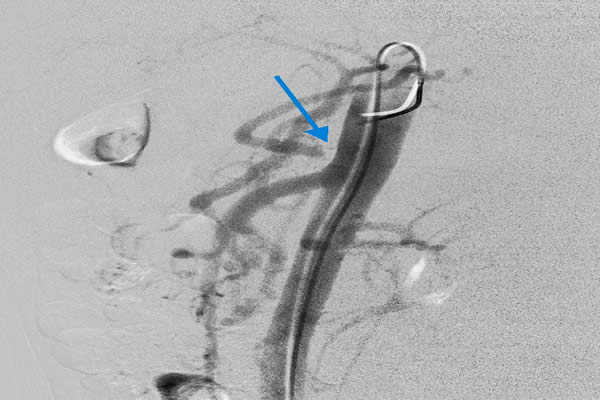

患者,女,62歲,以肝癌肝內(nèi)廣泛轉(zhuǎn)移收住入院,已無(wú)外科手術(shù)切除機(jī)會(huì),只能行介入化療栓塞術(shù)(TACE)。術(shù)中血管造影發(fā)現(xiàn)為肝臟供血的腹腔干已經(jīng)閉塞,導(dǎo)管無(wú)法進(jìn)入肝動(dòng)脈行介入化療栓塞術(shù),介入手術(shù)只能終止。由于已無(wú)其它治療方法,介入化療栓塞術(shù)終止,意味著患者只剩下1-2個(gè)月的生命??吹交颊吆图覍賹?duì)生命的渴望和對(duì)我們介入醫(yī)生的高度信任,我們不甘心就此放棄手術(shù)和延長(zhǎng)患者生命的機(jī)會(huì)。任小軍副主任反復(fù)研究血管造影圖像,見患者腸系膜上動(dòng)脈有側(cè)枝循環(huán)供應(yīng)到肝動(dòng)脈,仍有希望通過細(xì)小迂曲的側(cè)枝循環(huán)繞到肝動(dòng)脈進(jìn)行肝癌化療栓塞術(shù),但路途遙遠(yuǎn),操作復(fù)雜,手術(shù)時(shí)間長(zhǎng),醫(yī)生接受射線輻射大幅增加,并且成功的可能性很小,但是不嘗試,就沒有成功的機(jī)會(huì)。與家屬深入溝通后,任小軍副主任和任雪會(huì)副主任醫(yī)師反復(fù)耐心操作微導(dǎo)管,在技師和護(hù)士的高度配合下,導(dǎo)管終于成功進(jìn)入肝固有動(dòng)脈和肝右動(dòng)脈,對(duì)患者成功實(shí)施了介入化療栓塞術(shù),術(shù)后攝片和CT掃描顯示栓塞的碘油和化療藥大量沉積于肝臟腫瘤內(nèi),持續(xù)殺滅著腫瘤細(xì)胞?;颊咝g(shù)后反應(yīng)輕,恢復(fù)良好,現(xiàn)已出院。

這種腹腔干閉塞,通過腸系膜上動(dòng)脈側(cè)枝循環(huán)治療肝癌的病例少見,它技術(shù)難度大,需要深入插管到腸系膜上動(dòng)脈-回腸動(dòng)脈-胃十二指腸動(dòng)脈-肝固有動(dòng)脈-主要供血的肝右動(dòng)脈,導(dǎo)管在腸系膜上動(dòng)脈內(nèi)反復(fù)操作,出現(xiàn)腸系膜上動(dòng)脈夾層并引起腸梗死的風(fēng)險(xiǎn)大,手術(shù)時(shí)間長(zhǎng),介入醫(yī)生接受射線輻射多,一般都會(huì)終止治療。為了讓患者獲得最佳療效而延續(xù)生命,我們不放棄,敢創(chuàng)新,即使只有1%的希望也要付出100%的努力。對(duì)于一個(gè)醫(yī)生,沒有什么比延續(xù)患者生命更重要,沒有什么比延續(xù)患者生命更令人驕傲和自豪!